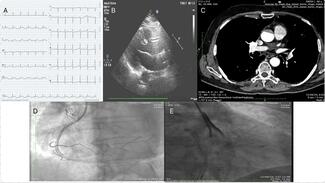

Lavina Chandwani, MD, DM; Anwar Hussain Ansari, MD, DM; Devesh Kumar, MD, MRCP, DM

A 52-year-old man presented to our emergency department with chest pain and diaphoresis for the past 4 hours. The pain was maximum at onset, retrosternal, and was radiating to his back.